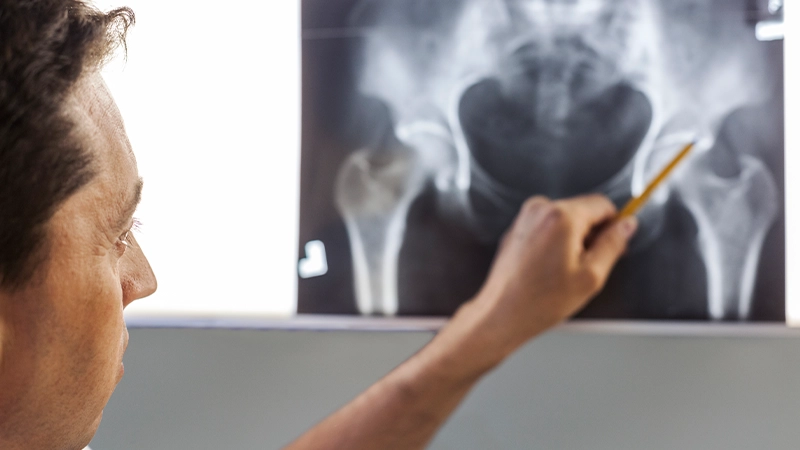

Diagnosis and Evaluation:

When assessing hip osteoarthritis, doctors take the patient’s history and perform a physical examination. They also examine the degree of pain and joint mobility. Imaging techniques such as X-rays, MRIs, or CT scans are often used to make a definitive diagnosis. These imaging techniques reveal the degree of arthritis, cartilage damage and osteophytes in the joint.